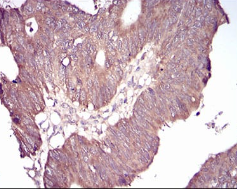

IHC    1/200 - 1/1000